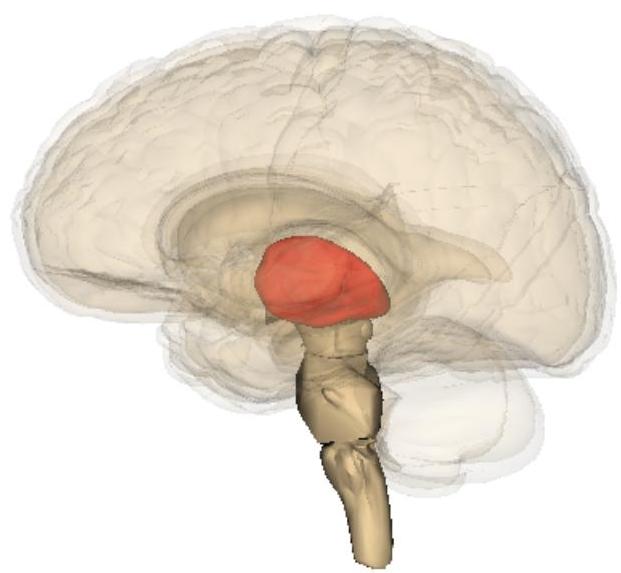

Akinetic Mutism

- Silent, immobile but alert appearing.

- Patients are in a wakeful state of profound apathy

- Seemingly indifferent to pain, thirst, or hunger.

- Usually due to lesion in:

- bilateral mesial frontal lobes

- bilateral thalamic lesions

- lesions in periaqueductal grey (brainstem)

Many cases of akinetic mutism have occurred after a thalamic stroke